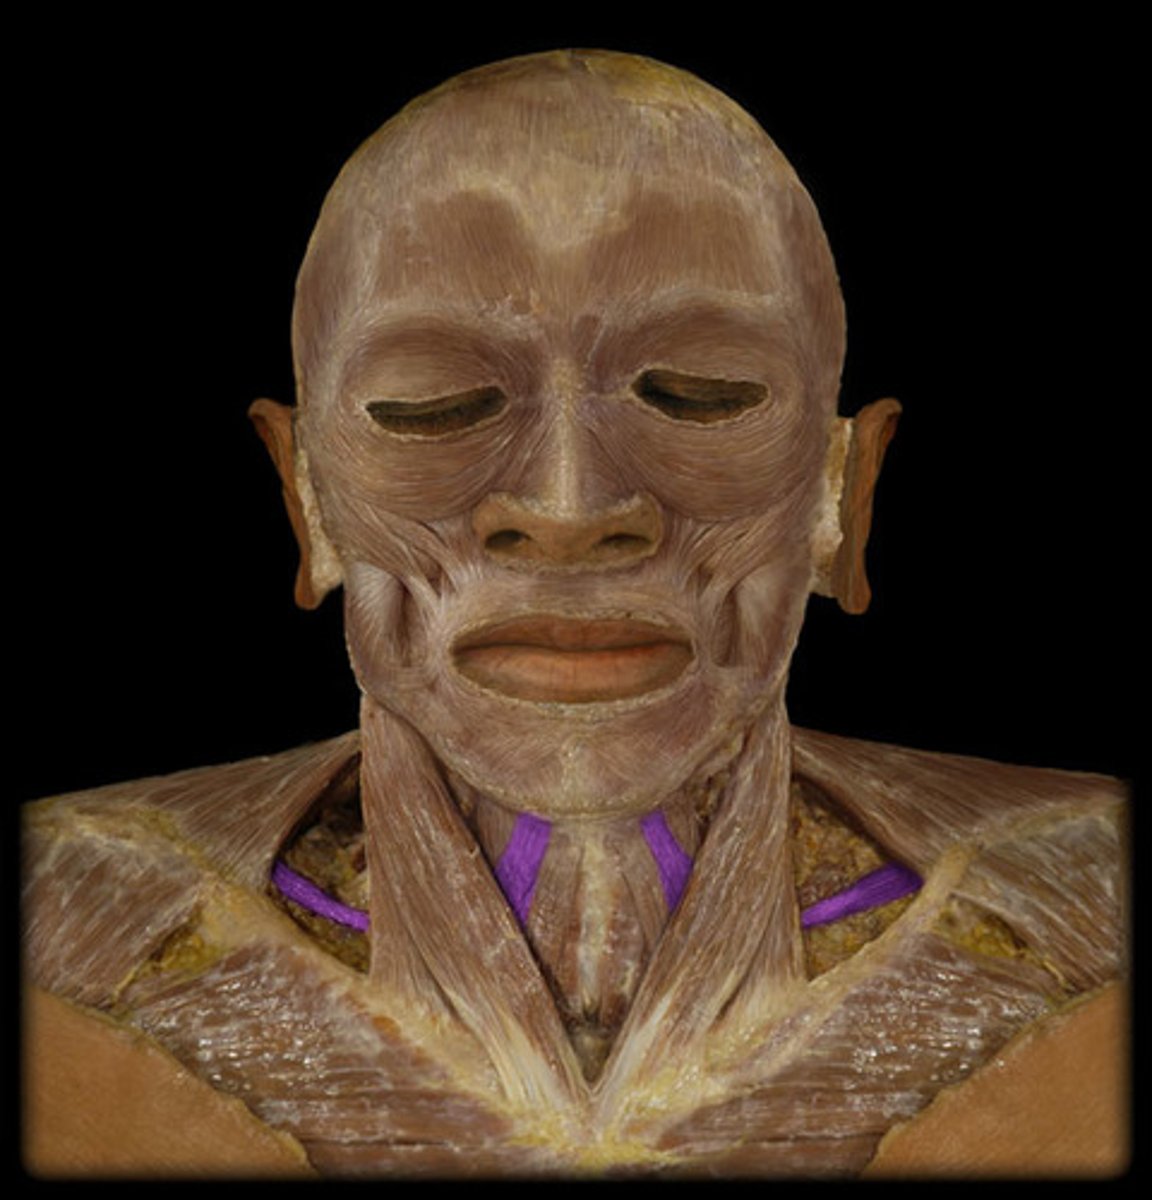

Platysma

Origin: Fascia of deltoid and pectoralis major

Insertion: Mandible, skin and subcutaenous tissue of lower face

Action: depresses mandible, draws angle of mouth downward (pout), tightens skin of the neck

Sternocleidomastoid

Origin: Manubrium of sternum; medial 1/3 of clavicle

Insertion: Mastoid process of temporal bone

Action: head tilt, rotating head

Scalene

Origin: Transverse process of all cervical vertebrae

Insertion: Ribs 1-2

Action: helps breathe by elevating upper ribs, flexes head, rotates head side to side

Digastric

Origin: Anterior Belly: Diagastric fossa of mandible: mastoid process of temporal bone

Insertion: Hyoid one via fascial sling

Action: depresses mandible, opens the mouth (when hyoid bone is fixed)

Stylohyoid

Action: elevates hyoid bone

Origin: styloid process of temporal bone

Insertion: hyoid bone

Sternothyroid

Origin: Manubrium of sternum; medial end of clavicle

Insertion: Thyroid cartilage of larynx

Action: Depresses larynx after it has been elevated in swallowing and vocalization

Omohyoid

Origin: Superior border of scapula

Insertion: Hyoid bone

Action: Depresses hyoid after being elevated